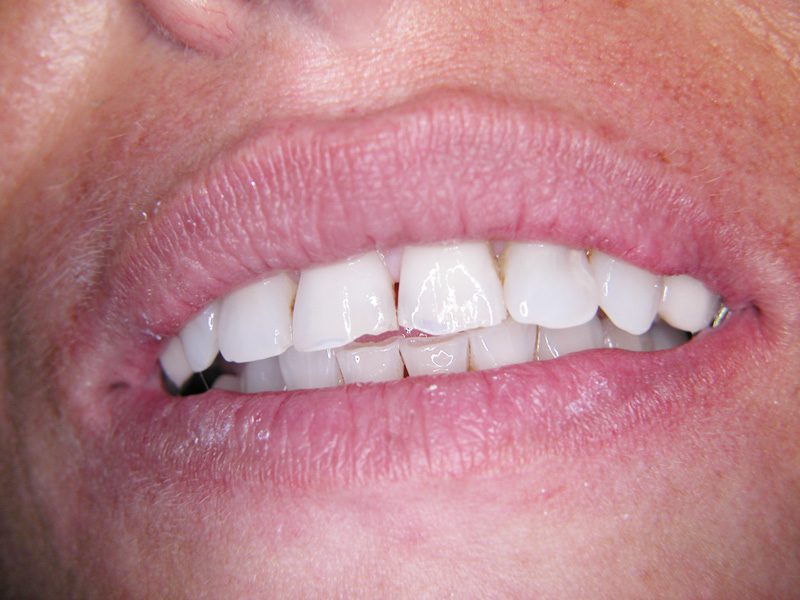

Implante - Galerie Foto

Caz II